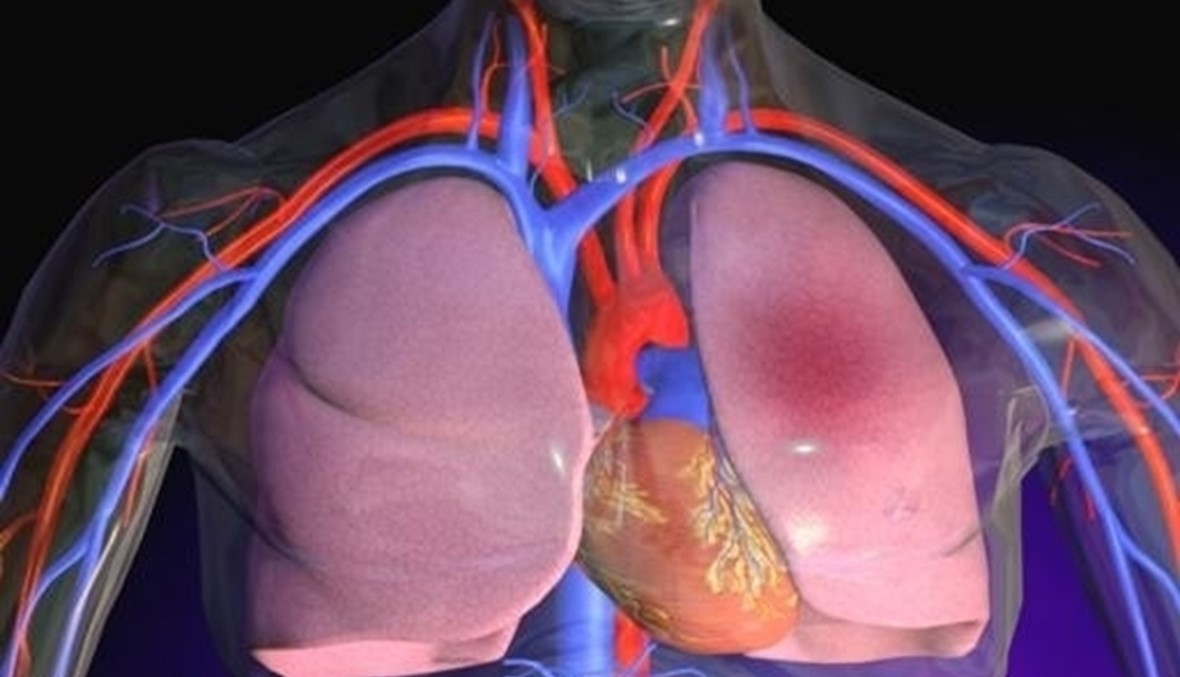

أحيت الجمعية اللبنانية للأمراض الصدريّة بالتعاون مع GlaxoSmithKline اليوم العالمي للانسداد الرئوي الناجم في شكل أساسي عن التدخين، سواء السجائر أو النرجيلة، كاشفة أن ثلاثة ملايين إنسان يموتون سنويا بسبب الانسداد الرئوي أكثر من نصفهم لم يكن يعرف أنه مصاب.

وأظهرت الدراسات أن9.7 % من اللبنانيين الذين تجاوزوا الأربعين سنة مصابون بهذا الداء، متجاوزين بكثير المعدّل العام في الشرق الأوسط الذي بلغ 4%.

وفي المؤتمر الذي عقدته الجمعية تحت شعار "لم يفت الأوان" عرضت الدكتورة ماري لويز كونيسكي نتائج دراسة، هي الاولى من نوعها في المنطقة، أظهرت أن ثلاثة عشر مليون إنسان في الشرق الاوسط مصابون بالانسداد الرئوي.

وحذّرت الدراسة من أن الوضع سيزداد سوءا في لبنان لأن 54% بالمئة من اللبنانيين الذين بلغوا الأربعين عاما هم من مدخّني السجائر أو النرجيلة أو الاثنتين معا، وما يزيد من تدهور الوضع هو أن أقل من ثلث المصابين يتم تشخيص حالهم وإخضاعهم للعلاج الملائم.